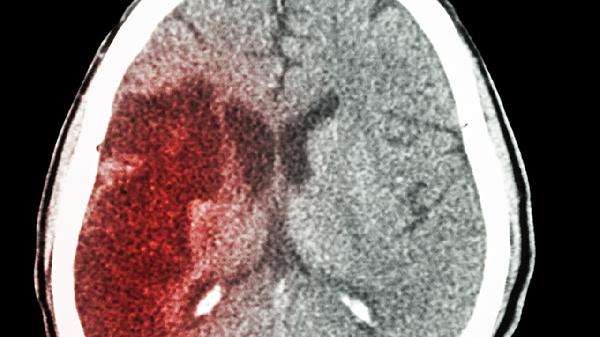

混合型譫妄兼具亢進(jìn)與抑制癥狀的交替出現(xiàn),臨床表現(xiàn)復(fù)雜多變。常見于多器官功能衰竭、中樞神經(jīng)系統(tǒng)疾病晚期患者,病情往往更為嚴(yán)重。治療需聯(lián)合對(duì)癥支持與病因治療,可考慮小劑量喹硫平片調(diào)節(jié)神經(jīng)遞質(zhì),同時(shí)加強(qiáng)營(yíng)養(yǎng)支持和感染防控,需警惕病情進(jìn)展為不可逆腦損傷。